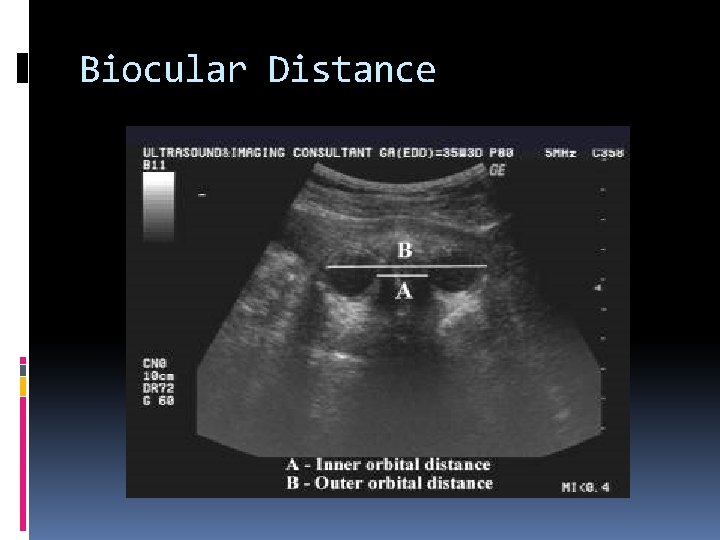

Binocular distance: measured from lateral orbital rim to lateral orbital rim. May be useful in assessing Gestational age in growth restricted fetuses, or when obtaining other head measurements is impossible Due to fetal position / cannot obtain a proper BPD

Biocular Distance